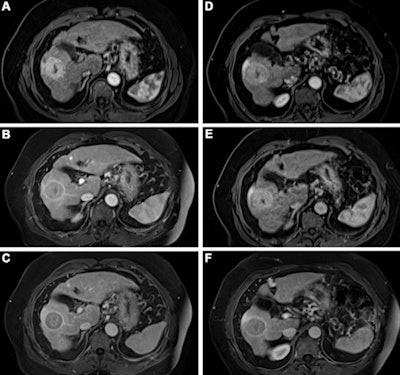

The high stability of gadopiclenol and lower injected dose make it suitable for patients who undergo repeated contrast-enhanced MRI examinations, such as hepatic MRI for the surveillance of patients with liver cirrhosis or cerebral MRI for patients with multiple sclerosis, they added. Also, when contrast-enhanced MRI is used on a population-wide scale, environmental issues will become even more important because GBCAs are excreted via the urinary tract and thus enter the wastewater.

Kuhl's group compared the performance of gadobutrol to gadopiclenol for lesion evaluation via a study that included 260 participants who underwent both gadopiclenol- and gadobutrol-enhanced MRI and had at least one identified lesion. Most patients presented with neoplasms (66%), and the most frequent of these were liver metastases and breast cancer.

The gadopiclenol exam was performed with 0.05 mmol/kg of contrast, while the gadobutrol exam was performed with 0.1 mmol/kg. The exams were read by 18 readers divided into three reading groups to compare the two contrast agents.

The investigators found that gadopiclenol at half the dose of gadobutrol performed comparably for all qualitative visualization parameters and for all readers. The majority of readers across the three groups (ranging from 75% to 83%) reported no preference between the two agents for image quality.